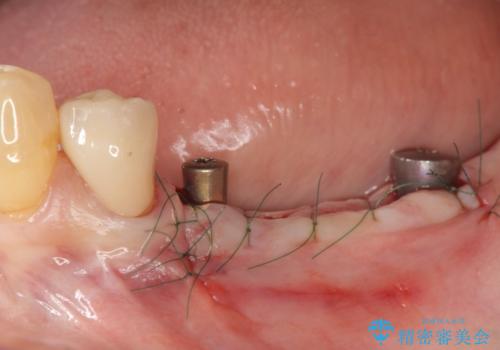

臼歯部の欠損 インプラント補綴

- 「奥歯がたくさん無くなってしまい、食事が楽しめるようにしっかりとかめるようにしてほしい。」という希望で来院されました。

入れ歯かインプラント治療の選択肢をご案内ししっかりと咀嚼機能を回復できる、インプラント治療を希望されました。

骨の量が比較的十分に保たれていたため、インプラントを埋入し1ヶ月後には仮歯を入れてしっかりと咬合機能を回復することができました。